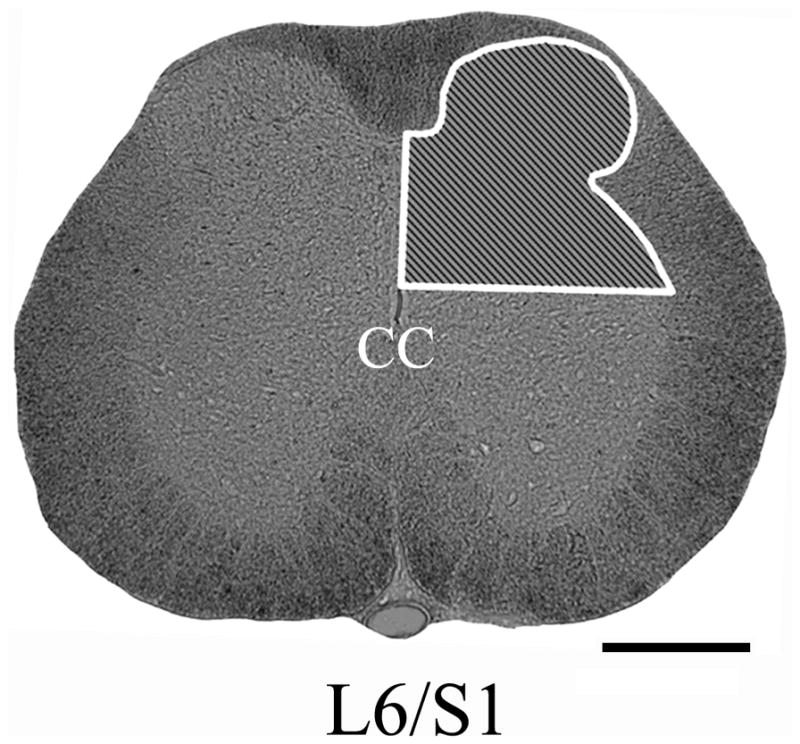

All sections were photographed with the same 10x objective magnification (10x eye piece) and with the same exposure settings. In all sections analyzed, our region of interest encompassed the unilateral (right) dorsal gray matter above the central canal, including Lissauer’s tract (LT) on the surface of dorsal horn (Fig. 1). Since CTb-labeled cells were seen in the sacral parasympathetic nucleus (SPN), this region was excluded from all densitometric analyses (see Discussion, Methodological considerations). For each animal, three serial spinal cord sections separated by 1 mm and centering on the L6/S1 level, as identified by cytoarchitecture, were selected for quantification. To measure CTb+/CGRP+/RT97+ immunoreactivity, labeled fibers were “thresholded” on each digital photograph, using the Bioquant program. For each section, the percent area occupied by immunolabeled fibers was calculated as the ratio of immunoreactive area divided by the region of interest area in unilateral dorsal gray matter x 100. The mean percentage of immunoreactive area occupied in three sections was calculated, followed by the mean for all animals in a treatment group.

Fig. 1.

Photomicrographs illustrating our region of interest for quantification (shaded inset) of CGRP+, RT97+, or CTb+ fiber density in the right upper dorsal gray matter at the L6/S1 spinal level. Scale bar=500 μm. CC, central canal.